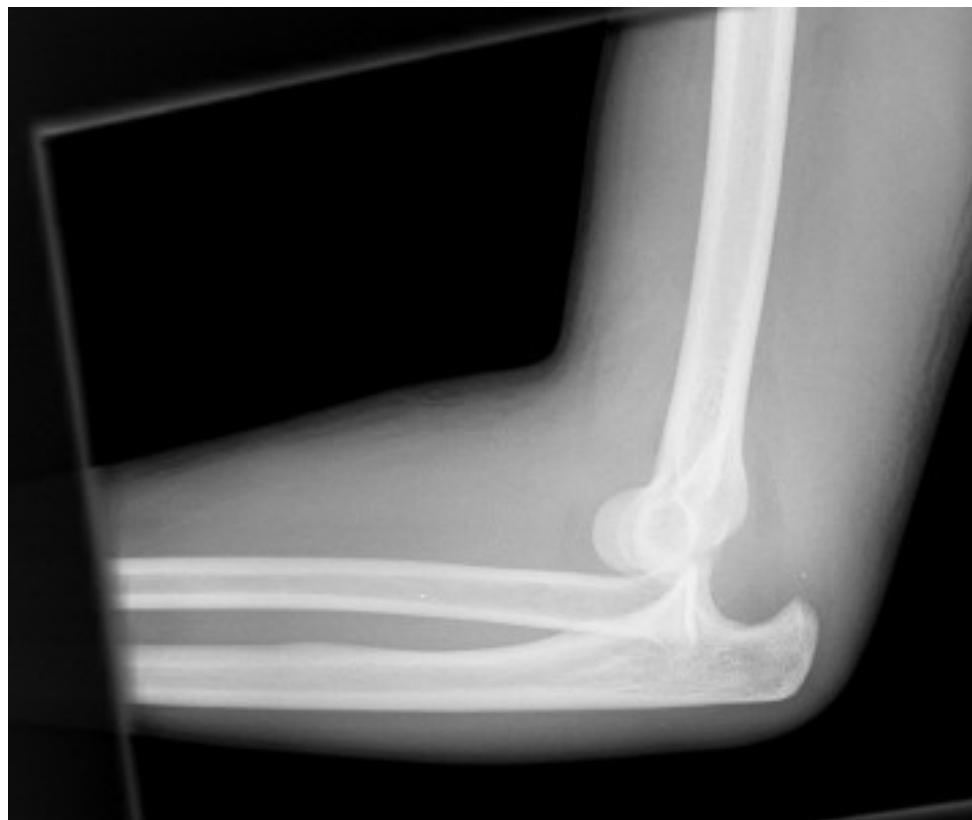

Elbow/Shoulder Dislocation

- Elbow Dislocation: Check for median/ulnar nerve or brachial artery injury. (1st image)